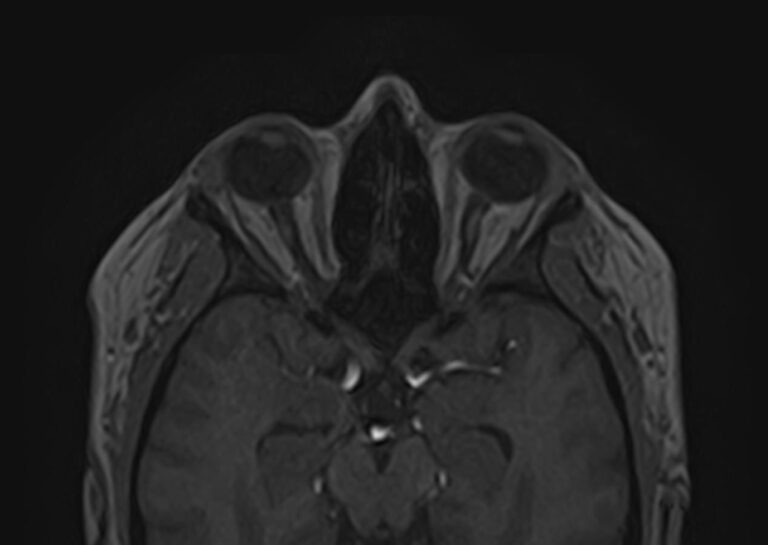

При необходимости визуализации всех отделов головного мозга с прицельным исследованием орбитальной области в клинике «Доступная медицина» проводится комплексное исследование — МРТ головного мозга + МРТ орбит. Это два отдельных исследования, каждое из которых имеет свой протокол сканирования, но при этом они могут проводиться в одно время.

Глазницы (орбиты) — это углубления в лицевом черепе, в которых расположены глазные яблоки, жировая клетчатка, мышцы глаза со связочным аппаратом, слезные железы, зрительные нервы. Волокна зрительных нервов проходят через анатомические отверстия глазниц в полость черепа, затем после частичного перекреста направляются к подкорковым зрительным анализаторам, а от них нервные окончания идут к зрительным центрам коры головного мозга в затылочной области.

Зрительный путь достаточно длинный и на всем его протяжении могут возникнуть патологические процессы, которые становятся причиной нарушения зрения. Иногда это связано с патологией другой области головного мозга, например, опухолью гипофиза. Поэтому в ряде случаев необходимо провести одновременное сканирование глазных орбит и головного мозга, чтобы выяснить, на каком отрезке пути произошло поражение, которое привело к снижению зрения.

Что покажет МРТ головного мозга + МРТ орбит

При обследовании головного мозга и орбит можно выявить:

• Опухоли орбит, воспалительные изменения глазного яблока и его придатков.

• Атрофию зрительного нерва, отслойку сетчатки, инородные тела орбитальной области.

• Объемные образования головного мозга или гематомы, сдавливающие зрительные пути.

• Очаги ишемического инсульта, кровоизлияние после геморрагического инсульта в подкорковых структурах, где расположены зрительные анализаторы, либо в затылочных долях, где находится зрительная кора головного мозга.